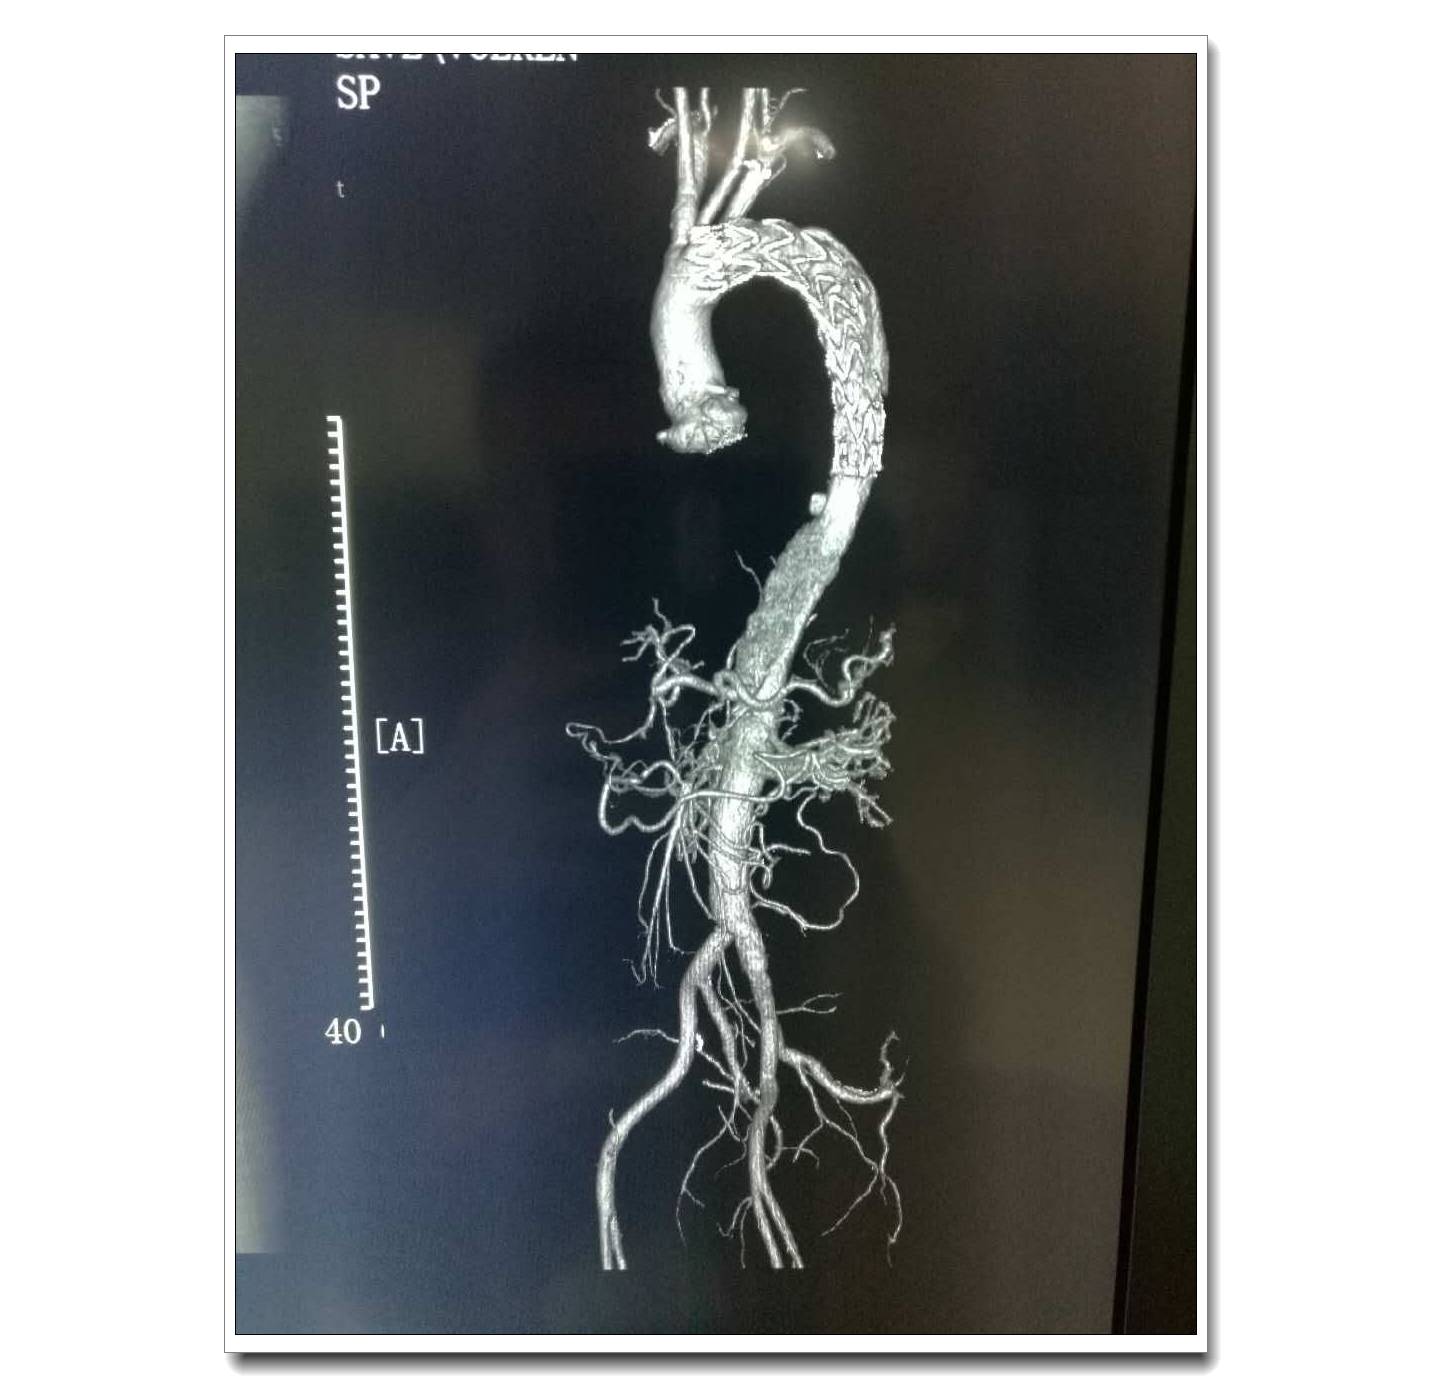

患者術(shù)前主動脈造影圖片

患者術(shù)后CT三維重建圖片